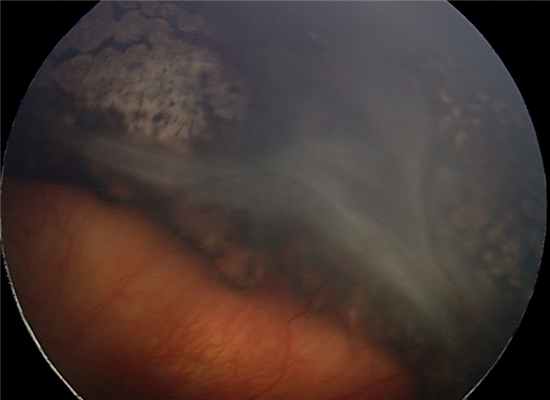

Глазное дно ребёнка А. до операции.

Глазное дно ребёнка А. после операции.